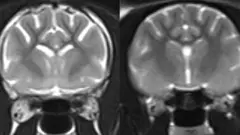

Imagens de microscopia de gatos mais velhos que anteriormente apresentaram sintomas de demência felina revelaram um acúmulo de beta-amiloide nas sinapses — as junções entre as células cerebrais.

Crédito, University of Edinburgh

As sinapses permitem a passagem de mensagens entre as células cerebrais, e a perda delas causa redução da memória e das habilidades de raciocínio em humanos com Alzheimer.